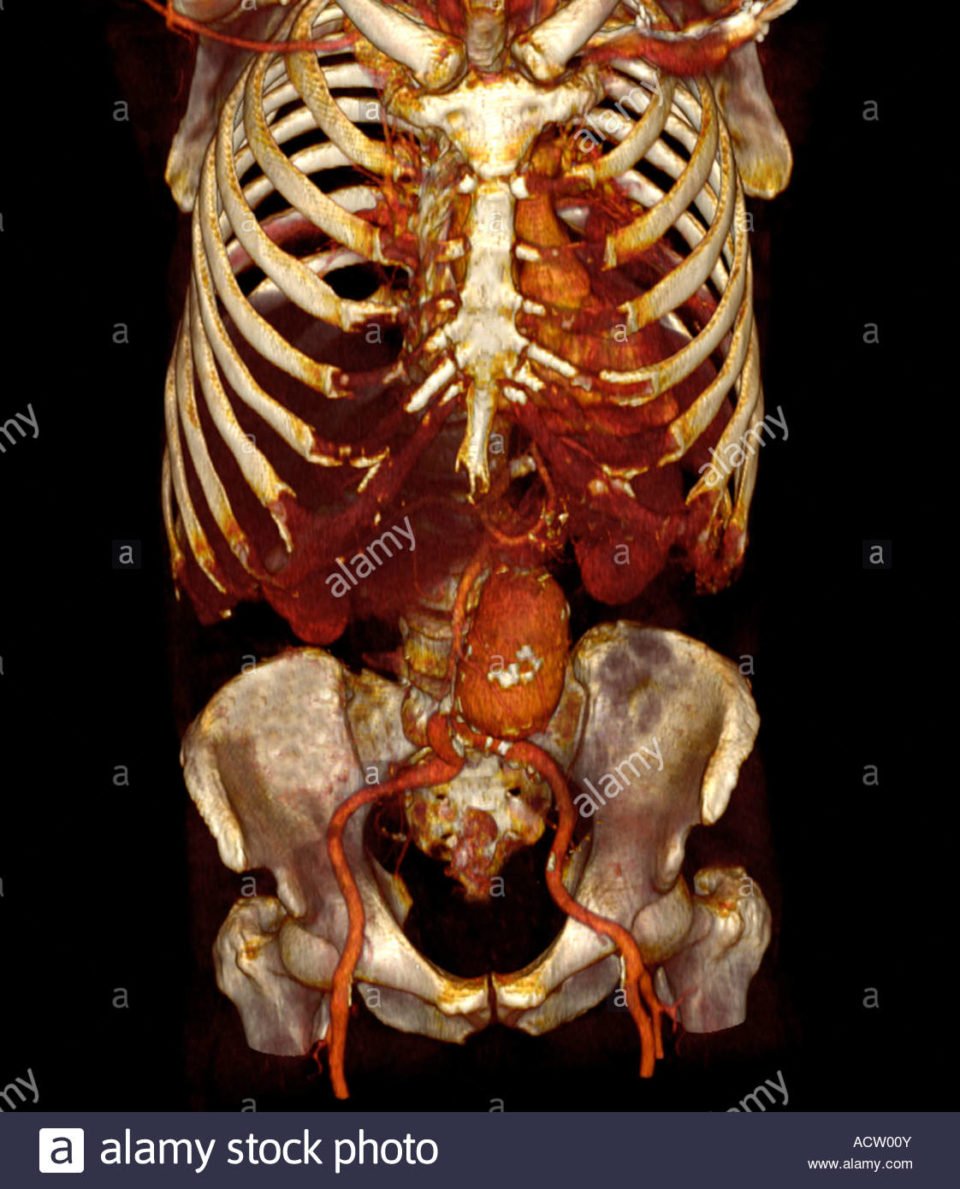

L’aorte est le plus gros vaisseau de l’organisme, sa partie située dans l’abdomen se divise en deux artères iliaques pour apporter le sang aux 2 membres inférieurs. L’anévrisme de l’aorte abdominale est une dilatation ou une augmentation de calibre de l’aorte abdominale. On parle d’anévrisme lorsque le diamètre de l’aorte mesure plus de 30 mm (3 cm) et d’anévrysme iliaque lorsque le diamètre de l’artère iliaque mesure plus de 20 mm (2 cm).

La grande majorité (85%) des anévrismes de l’aorte abdominale est située sous les artères rénales et les artères iliaques sont souvent aussi anévrismales. Si l’anévrisme englobe l’origine des artères rénales, on parle alors d’anévrisme pararénal.

L’angioscanner aorto-iliaque est plus invasif mais plus reproductible que l’échographie et moins opérateur dépendant. C’est l’examen de choix avant un traitement par endoprothèse ou par chirurgie classique. Il permet les mesures exactes (« sizing ») de l’anatomie de l’anévrysme, de l’aorte et des artères iliaques avant mise en place d’une endoprothèse. Il permet la recherche d’autres anévrysmes au niveau fémoro-poplités et d’étudier l’ensemble de l’aorte.